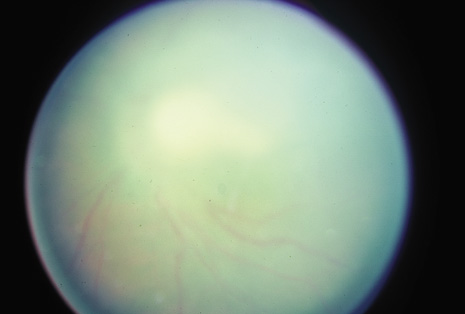

Many forms of uveitis are characterized by specific types of inflammatory cells. Usually, however, one encounters mixtures of cell types in any given specimen, with the relative percentages of lymphocytes and polymorphonuclear leukocytes varying. There may be unusual numbers of eosinophils, or macrophages laden with lens material may be present. Thus, an enumeration of the cells and a careful analysis of their structure can be useful as a diagnostic aid (Figs. 7, 8, 9, 10, 11, 12, 13, 14, 15, 16, 17, 18, 19, and 20). Figure 15 demonstrates eosinophils that were aspirated from the anterior chamber of a patient with Toxocara canis endophthalmitis. Figure 12 demonstrates malignant cell infiltrate from the vitreous, showing the stained presence of monoclonal light chains being elaborated in the cytoplasm. Interleukin-10, detectable in the vitreous of intraocular lymphoma patients, is also directly indicative of both the clinical activity and the number of malignant cells as observed by cytopathology.

Precise identification and culture of bacterial and fungal pathogens from both the aqueous humor and the vitreous fluid can be obtained. Gram's stain and Giemsa's stain smears of centrifuged specimens from the aqueous humor and the vitreous humor frequently demonstrate the bacterial or fungal causative agent. Attempts to isolate bacteria and fungi and to identify them on Gram's stain or Giemsa's stain smears have been most rewarding in the following cases: (a) postoperative endophthalmitis, (b) infection after a penetrating injury of the eye, (c) drug abuse patients with endogenous endophthalmitis (Figs. 21, 22, 23, 24, and 25), (d) patients receiving hyperalimentation, and (4) patients who are immunocompromised as a result of exogenous immunosuppressive agents.

Studies have demonstrated the usefulness of ocular paracentesis for the identification of ocular infections in order to implement sight-saving treatment.10–16 Even acid-fast bacilli and viruses may be diagnosed in this fashion when emergency dictates (see Fig. 5).17 It is recommended that diagnostic paracentesis be performed in all cases of postoperative endophthalmitis, and it is safe to perform the postoperative procedure in the operating room with the safety of vitrectomy surgery. Further, any patient older than 65 who presents with a deteriorating uveitis (usually with vitreitis as the predominant infiltrate) of undetermined etiology should undergo paracentesis of the vitreous to rule out reticulum cell sarcoma (large cell lymphoma).18 Similarly, any patient suspected of being an intravenous drug abuser who presents with an endogenous endophthalmitis or uveitis should undergo diagnostic paracentesis to avoid allowing an intraocular infection to be borne by the bloodstream.19,20